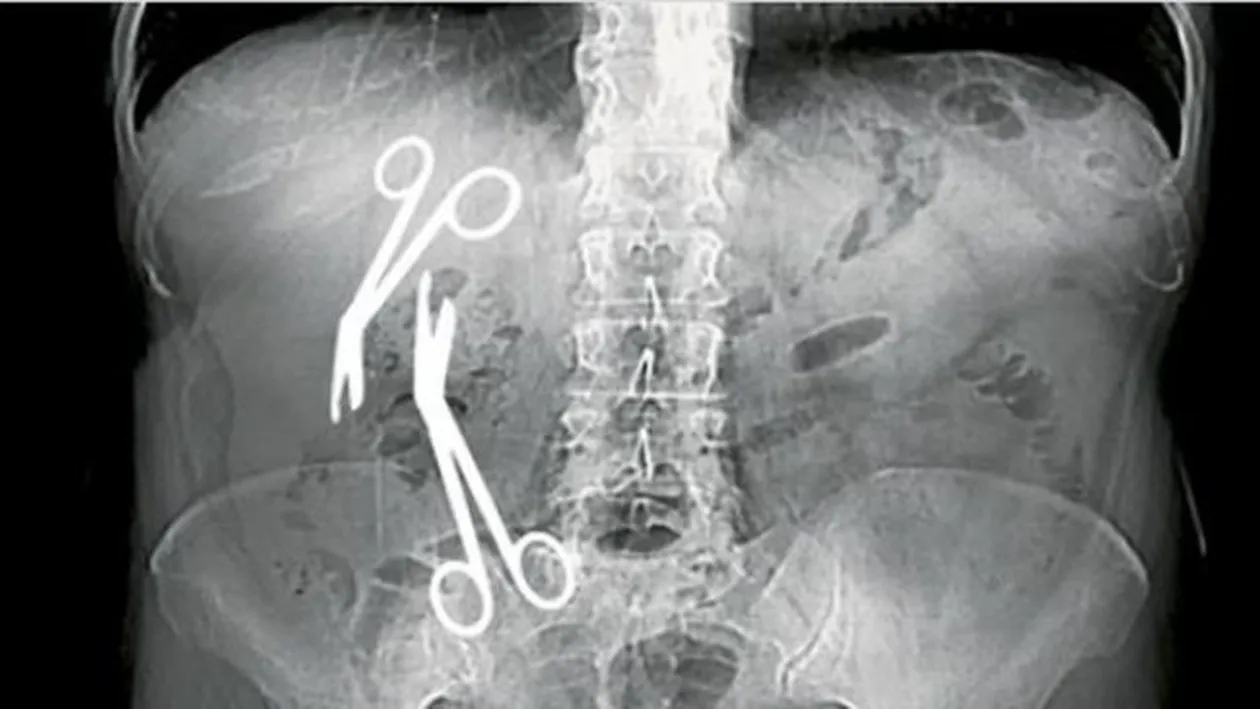

Directorul medical al Spitalului Militar din Constanța, Gheorghe Ștefan, este acuzat că a uitat două perechi de foarfece în burta unei femei, scrie libertatea.ro.

Potrivit concluziilor examenului CT, publicate de ziarul „Libertatea”, în corpul pacientei au fost descoperite „două corpuri străine radioopace (foarfece) cu diametrul axial de 158 mm în cavitatea abdominală: hipocondru drept şi fosa iliacă dreaptă”.

O foarfecă se află în zona ficatului, iar cealaltă în zona apendicului.